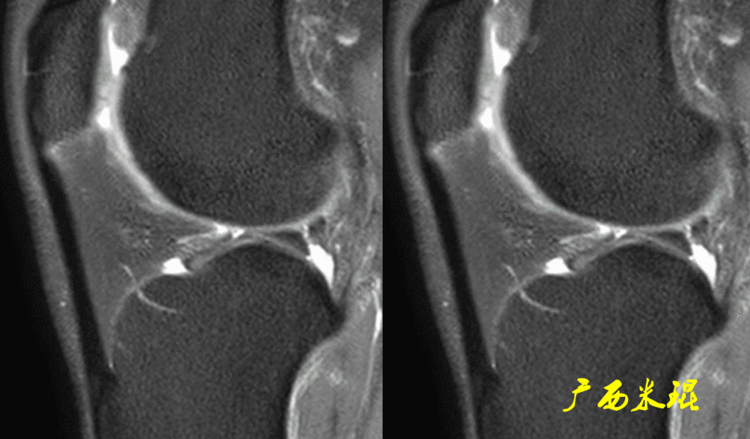

7、半月板后角内侧半月板周径较大,形似“C”形,后角宽,前角窄,后角宽度几乎是前角的2倍;外侧半月板周径小而面积大,形似“O”形,中部宽阔,前后角匀称,而且内外侧半月板后角为了适应内外侧胫骨髁和股骨髁而有着不完全相同的形态。

(1)假桶柄MR冠状位上偏后的层面,“C”形或“O”形的内外侧半月板偏后侧层面有可能同时扫描到半月板体部和后角,容易误诊为桶柄状撕裂,而矢状位或横断位上半月板形态是正常的。

下面这张MR冠状位显示为内侧半月板后角的假桶柄,其母体(图片中内侧的那一部分半月板)并没有变小、形态及信号均正常。

下面这张MR冠状位显示为外侧半月板后角的假桶柄,尽管在髁间窝发现半月板信号,但其母体(图片中外侧的那一部分半月板)并没有变小、形态及信号均正常。